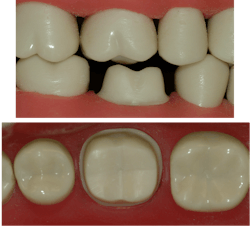

Zirconia crowns are the most popular crown type in the US (figure 1). What can cause the disagreeable situation of crowns coming off? Here are the most important reasons:

Tooth preparation. Many studies have been conducted to determine tooth preparation characteristics that produce optimum retention. If the preparation is for a tooth that was not previously prepared for a crown, the ideal characteristics are easily defined (figure 2). The axial walls of the prep should have 4 mm or more of sound tooth structure or secured buildup material from the cervical margin to the occlusal table on all four axial walls. The prep should have no more than 20 degrees of taper from the tooth’s long axis. These characteristics are often not possible if the tooth has not fully erupted or is in a location (such as mandibular second molars) with only short clinical crowns present. The solution to this condition will be discussed later.

- For short preps or those with too much taper (or both), increase the mechanical crown retention by having your technician place horizontal grooves in the intaglio surfaces of the crown in the presintered zirconia.

- For short preps or those with too much taper (or both), increase the mechanical retention on the prep by placing horizontal grooves on all four axial walls with a coarse diamond.